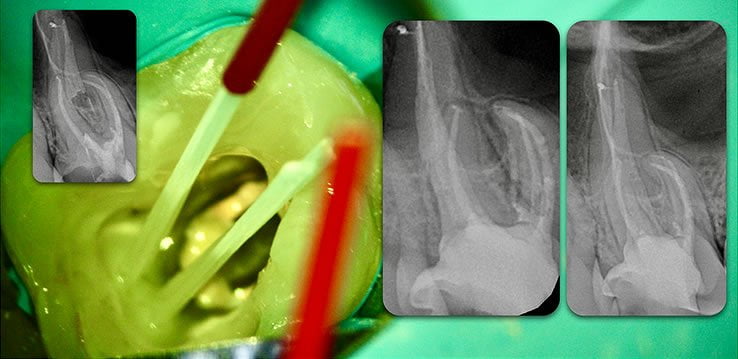

Template for x-rays

Biolight® DRILL-FREE posts are available in bundles of 4, 6, 9 and 12 strands. The post size is selected based on the width of the canal at the coronal area. Depending upon the canal width at the apical stop, a certain number of strands must be pushed to the stop. Both of the measurements are made with the assistance of a radiograph and the template that is included in the TRAINING KIT.